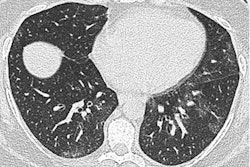

The true lung cyst is a well-defined, rounded lesion with a thin wall, usually containing air, and it can be an isolated abnormality or part of a cystic lung disease, noted Beddy, whose presentation focused on differentiating cystic lesions from emphysema.

Various entities cause air-filled cystic lesions which need differentiation on CT. Courtesy of Prof. Peter Beddy.He cautioned against dismissing isolated cysts as benign entities entirely because radiologists increasingly are recognizing a cystic tumor that develops from what has been described previously as a simple cyst. Multiple cysts, on the other hand, must trigger suspicion of cystic lung disease such as Langerhans cell histiocytosis or lymphangioleiomyomatosis. One of its main differentials, however, is emphysema.

Two key features are crucial to differentiation, Beddy explained. The first is the wall, which is not present in most emphysema, unless it is advanced and the result of fibrosis. In emphysema, however, this type of wall is usually incomplete and therefore can be differentiated from a lung cyst. The second is the presence of internal architecture which in centrilobular emphysema may present as a central dot, representing a vessel within the area of destroyed lung.

Centrilobular emphysema has no or very thin walls and a central dot. Courtesy of Prof. Peter Beddy."The key difference between centrilobular emphysema and a lung cyst is that emphysema lacks a perceptible wall in most cases, and will have an internal structure, whereas a cyst has a definable wall and no internal structure," he said.

Radiologists should therefore ask themselves: Does the lesion have internal contents? Does it have a wall? The essential point is to check this wall not just for differentiating centrilobular emphysema but also for ruling out other differentials.

Three top tips for determining pathology in air-filled cystic lesion. Courtesy of Prof. Peter Beddy.For example, lung cavities have thick irregular walls, whereas the subpleural lucencies of paraseptal emphysema often share very thin walls. Meanwhile, honeycombing presents as air-filled cystic spaces in peripheral and subpleural locations with well-defined walls, he noted.